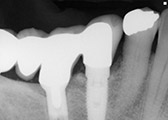

We are proud to offer dental implants for our patients. Dental implants are roots placed in your mouth for either permanent teeth to be placed on or ones that you can remove.